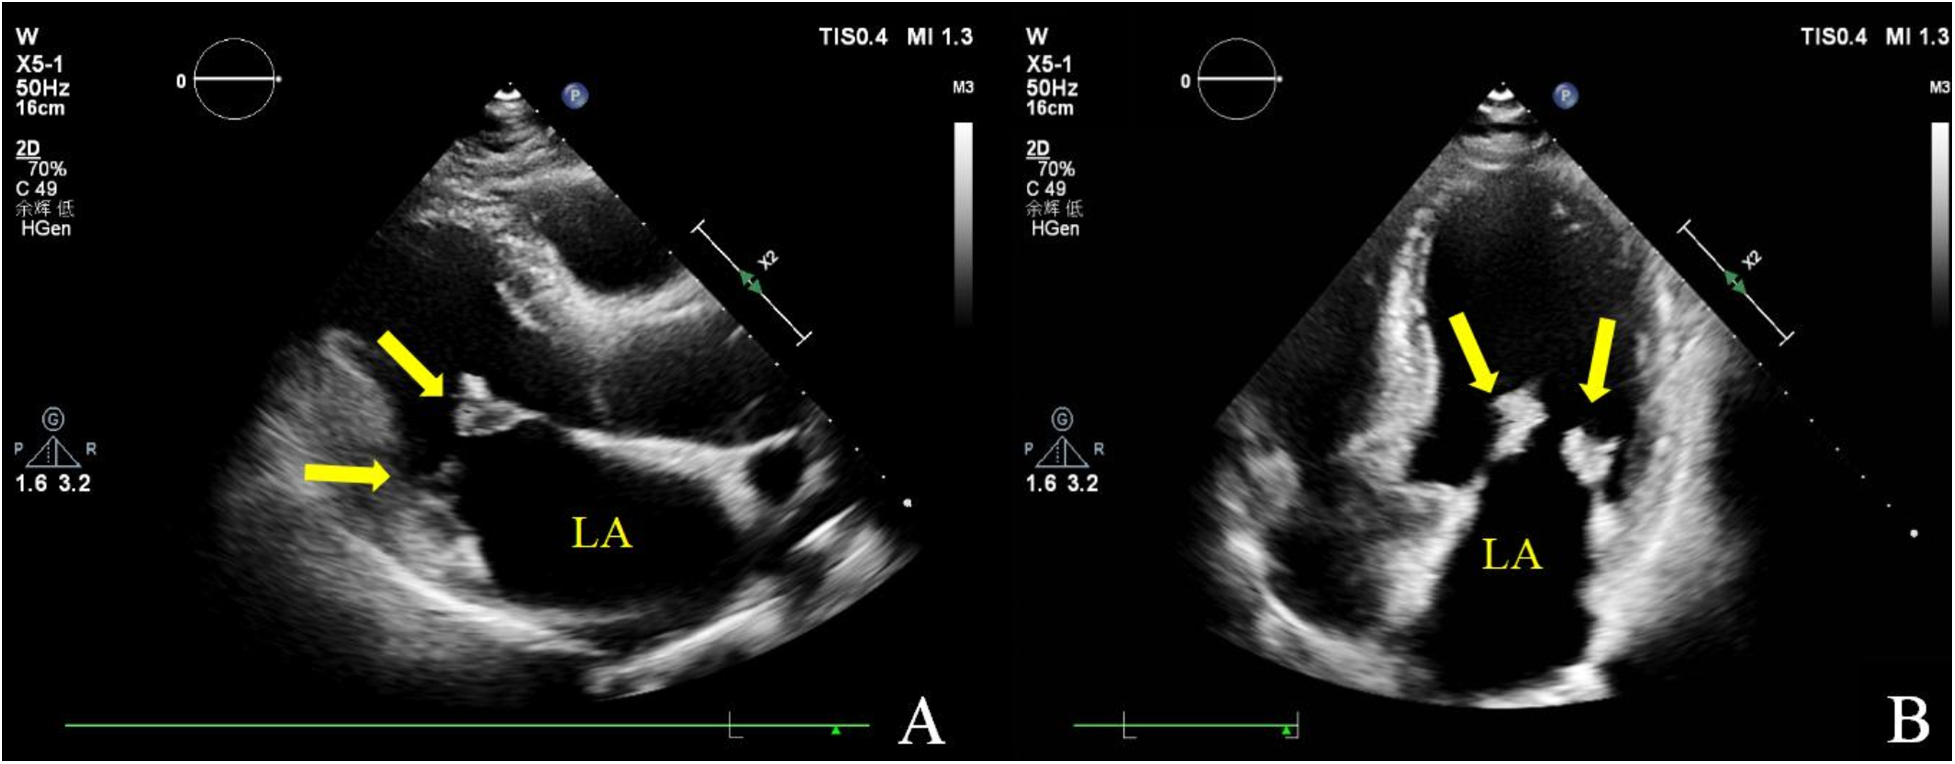

Figure 1

Transthoracic echocardiography. Multiple iso-echoic masses with irregular shapes were observed on the atrial sides of both the anterior and posterior mitral leaflets. Left ventricle long axis view (A) and apical four chamber view (B).

Two-dimensional transthoracic echocardiography (TTE) demonstrated left ventricular hypertrophy and left atrium enlargement. There were no segmental motion abnormalities. The patient’s left ventricular end-diastolic diameter (LVEDd) was 56 mm, his left ventricular end-systolic diameter (LVESd) was 40 mm, and his left ventricular ejection fraction (LVEF) was 57%. The anterior and posterior leaflets of the mitral valve were obviously thickened, especially on the edge area. Multiple iso-echoic neoplasms with irregular shapes were observed on the atrial sides of both the anterior and posterior mitral leaflets. The largest neoplasms were 14.6 mm × 12.0 mm on the anterior leaflet and 10.9 mm × 10.5 mm on the posterior leaflet, respectively (Figure 1). Color Doppler imaging showed moderate central mitral regurgitation (Supplementary Video S1). Laboratory tests showed no significant abnormalities in routine blood examination, coagulation, extractable nuclear antigen (ENA) antibody spectrum, liver function, and kidney function. Blood culture indicated no bacterial or anaerobic growth. A cranial CT scan suggested no signs of embolism in the brain. Computed tomography angiography (CTA) revealed the presence of calcified plaques on the thoracic and abdominal aortas, and also a lack of discernible indications of embolization. Infective and non-infective vegetations were ruled out based on these results. To further refine the neoplasm characterization, TEE was performed. TEE showed extensive thickening of the mitral valve, with multiple appendixes on the margins, with a smooth but irregular surface and a broad base attached to the anterior and posterior mitral leaflets (Figure 2). It seemed soft and deformed during valvular closure. Flickers could be seen with valve opening and closing, but without flail movement (Supplementary Video S2). Three-dimensional TEE revealed a diffuse distribution of granular neoplasms on the left atrial side of the mitral valve, especially two-thirds of the free edge area, as well as bilateral commissures. They were fused and the boundaries were unclear (Figure 2). The surface was cauliflower-shaped (Supplementary Video S3). There were no other valves involved in this case. Considering the risk of heart failure due to the valve disease and the risk of embolism, surgical treatment was performed. Intraoperative exploration showed that two-thirds of the area near the confluence margin of the anterior and posterior mitral leaflets were covered by diffuse tumor-like lesions. The commissural cusps and sub-valvular structures were involved as well, but there were no neoplasms on the left ventricular side of the leaflets. The lesions were merged with each other and characterized by a wider fundus and irregular shape. The granular structure partially extended toward the chordae tendineae. The impaired mitral valve was excised and submitted for histological examination and a microbiological culture. A prosthetic mechanical valve was replaced. An absence of bacterial proliferation was observed after a 48 h incubation for bacterial culture. The pathological examination showed a cauliflower-shaped protrusion approximately 2 cm × 1.5 cm × 1.2 cm in size on the excised mitral valve during the gross inspection (Figure 3). Under the light microscope, edema and mucinous degeneration were observed in the leaflet tissues, and there were spindle or stellate morphologic cells sparsely situated within an abundant mucinous matrix, which exhibited a mild morphology without abnormal nuclear division (Figure 3). The consultant pathologist suggested the diagnosis of a diffuse myxoma on the mitral valve with both leaflets, the commissural cusps, and the sub-valvular chordae tendineae extensively involved. The postoperative assessment indicated the prosthetic valve worked well (Table 1).